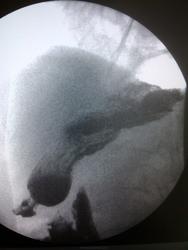

Пациент, 60 лет. На ФГДС: В антральном отделе отмечается некоторая ригидность на малой кривизне, рядом с привратником.

Не вижу изменений в антральном отделе, но обращает внимание некоторая ригидность задне-медиальной стенки субкардиально.

Обратила внимание на уплощение контура на малой кривизне препилорического отдела. Но только на одном снимке, на остальных - без особенностей. Вряд ли стоит придавать этому значение. Вы видели моторику - Вам судить